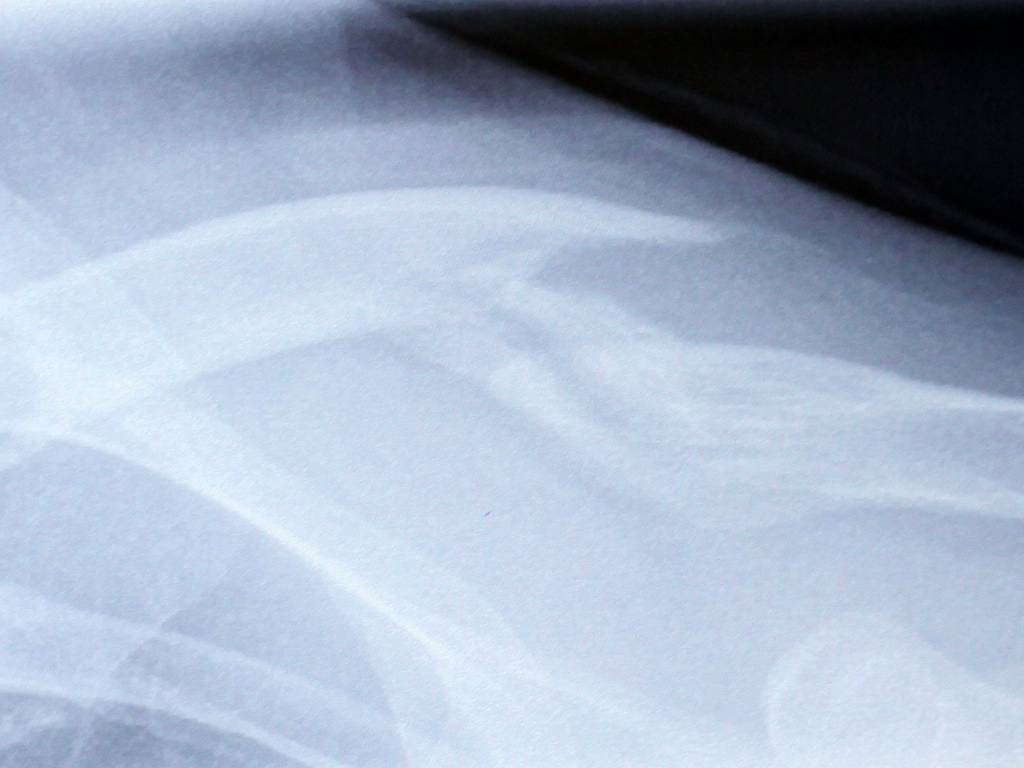

Here are some photos I snapped of the x-rays taken at the Ottawa General Hospital, at various points after my cycling accident:

T+19 days

[Update: 9 July 2010] Here is an x-ray from today, showing a bit more of the affected area. The biggest difference from the T+19 shot is the round area of bone forming underneath the fracture area. The doctor told me another should form later underneath that sharp protrusion:

T+40 days